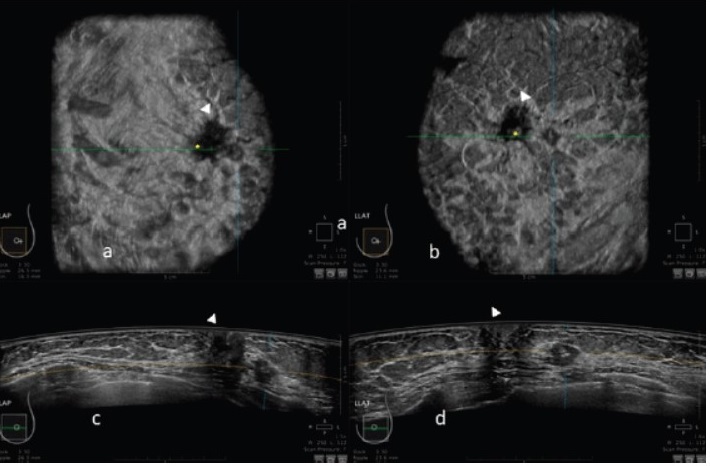

-تشخیص بیماریهای غدد پستان

اولتراسوند به عنوان یک ابزار تکمیلی در تشخیص و بررسی بیماریهای پستان مانند تومورها و کیستها استفاده میشود. این روش به پزشکان کمک میکند تا بین تومورهای خوشخیم و بدخیم تمایز قائل شوند.